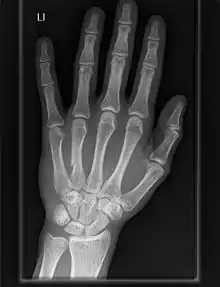

Carpometacarpal joint

The carpometacarpal (CMC) joints are five joints in the wrist that articulate the distal row of carpal bones and the proximal bases of the five metacarpal bones.

The CMC joint of the thumb or the first CMC joint, also known as the trapeziometacarpal (TMC) joint, differs significantly from the other four CMC joints and is therefore described separately.

Fingers

- The second metacarpal articulates primarily with the trapezoid and secondarily with the trapezium and capitate.

- The third metacarpal articulates primarily with the capitate,

- The fourth metacarpal articulates with the capitate and hamate.

- The fifth metacarpal articulates with the hamate.